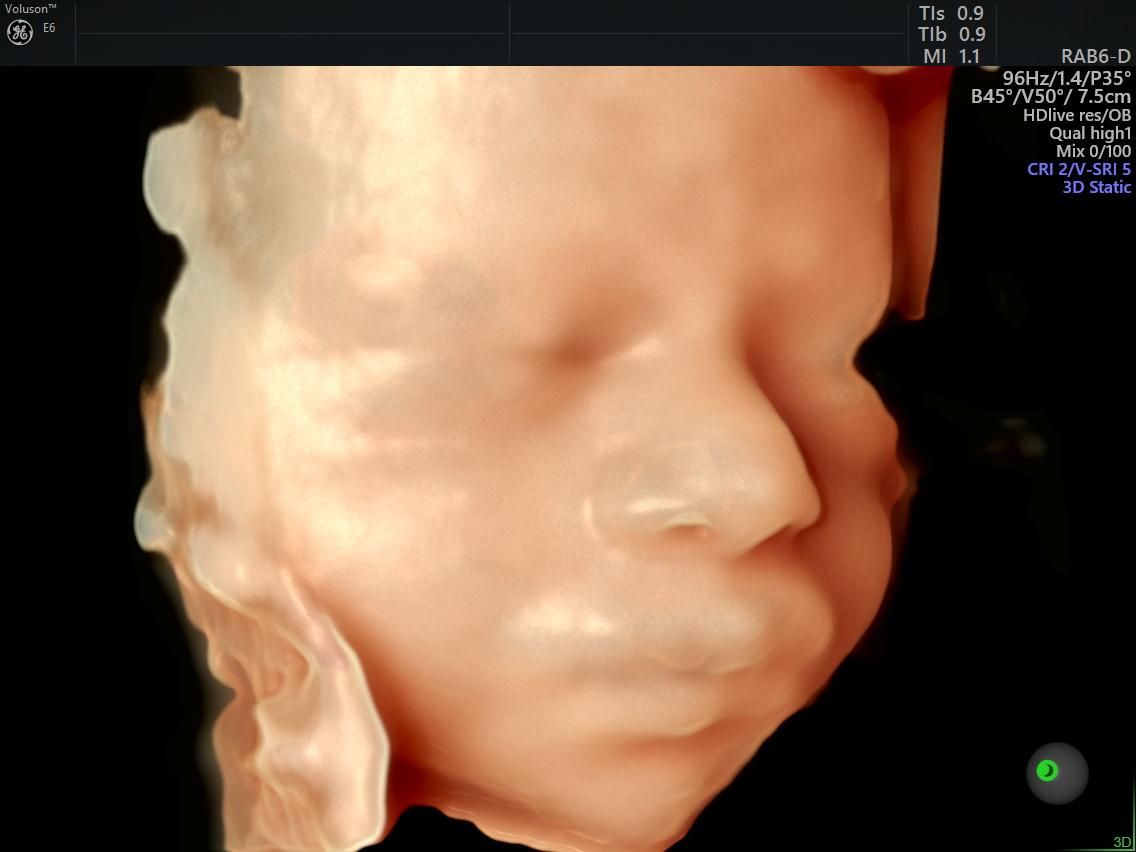

Cuento con experiencia en el manejo de embarazos de alto riesgo, incluyendo condiciones como diabetes gestacional, preeclampsia, restricción del crecimiento intrauterino y malformaciones fetales. Realizo estudios avanzados de ultrasonido, lo que me permite ofrecer una evaluación detallada del bienestar materno y fetal, así como un seguimiento individualizado para cada caso.

Fotos y videos

Me explicó y atendió excelente, despejo mis dudas, y pude ver a mi bebé de una forma que no creí posible en el ultrasonido, el mejor materno fetal de Aguascalientes!